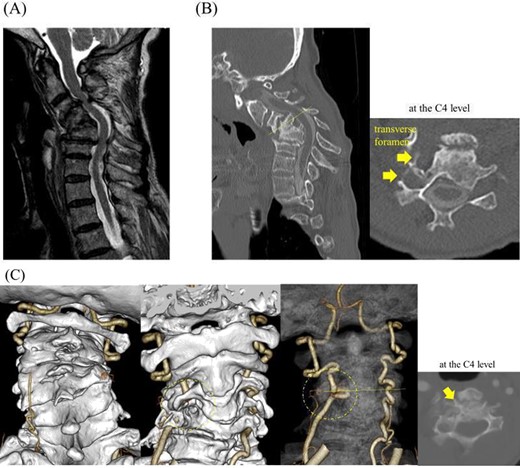

On clinical examination, we observed severe kyphosis (C2–7 angle: −65) with C4–6 fusion. Magnetic resonance imaging (MRI) and computed tomography (CT) myelography revealed C3/4 spinal canal stenosis with C3 anterior slip. Imaging showed two right transverse foramina at the C4 level and a tortuous right VA invaginating into the C4 vertebral body (Fig. 2).

CT myelography, MRI and CT angiography on admission; (A) stenosis at the C3/4 level with C3 anterior slip was observed on magnetic resonance T2-weighted images, and (B) the C4–6 vertebrae were fused into a single mass; note local kyphosis and scoliosis due to vertebral collapse, and a transverse slice at the C4 level showed two transverse foramina on the right side, and (C) the right VA invaginating into the C4 vertebral body was shown in a transverse slice at the C4 level on CT angiography.